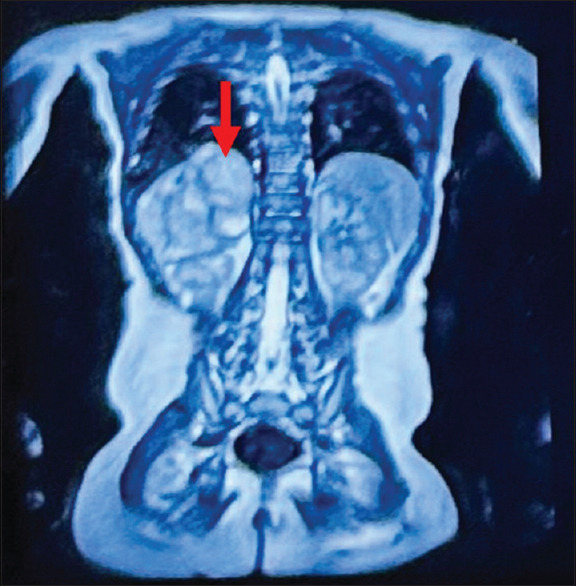

金斯伯恩综合征患儿神经母细胞瘤切除术的麻醉处理。

Anesthetic management of neuroblastoma excision in child with Kinsbourne syndrome.